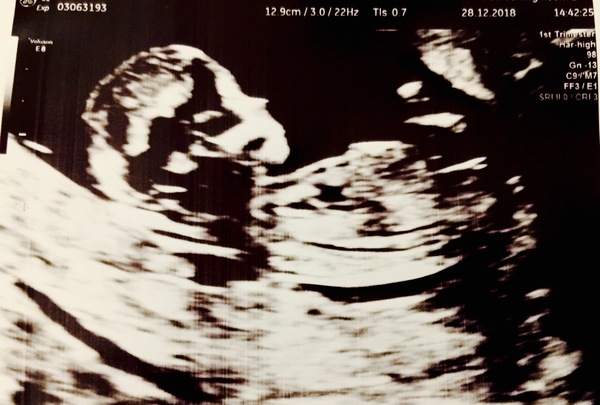

StargazyDrifter · 28/12/2018 18:12

Another good one! EDD brought back to 7/7/19, which is as I had always said going by my positive OPK. Seems that was more accurate than early EPU measurements this time.

What a drama lama already. When emptying my bladder didn't help get a better view, I had to jump up and down and sort of dance around halfway through the scan (not graceful, and with all that jelly going everywhere!) to get a better view of the baby for the sonographer. In the end we had to go with the internal scan, was there almost an hour! 🙈

The baby was lovely and we saw a few waves and a bit of gulping of the amniotic fluid (mmmm, looks delicious, not!). Big feet. I can't believe how defined everything is already. Delighted and a little bit incredulous to have got this far. 😆

Lovely scan @StargazyDrifter ! So cute! Do you know why they couldn't get a view abdominally? I'm a bit of a porker and am worried they won't be able to see through my jelly 😱😂

MakeAWhish I think it was because of the baby's position rather than jelly - anothe one for this thread's glossary! I always carry all my weight on my tummy, in a little pot belly, but they didn't seem to mind. The issue seemed to be that baby was 'standing up' and that position didn't allow a good view of the baby's heart and bladder (to think they are even there at this stage, let alone that they can be seen, is staggering). So I had to try and make it shift inside for a better angle, which it wouldn't! I suspecy any weight is fine as long as the angles are right.

StargazyDrifter · 28/12/2018 18:29

Twistering I meant to add, lovely scan and I'm pretty sure I can see your baby's hand in the background doing a gentle wave. 😍

Whoop @StargazyDrifter!! Wonderful! Completely understand the incredulous bit. And what a little tinker...already!